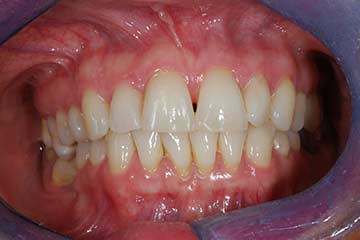

Con protesi fissa superiore e protesi fissa inferiore

I denti irrecuperabili dell'arcata superiore ed inferiore del paziente di anni 65

sono stati sostituiti da 10 impianti, cioè protesi radicolari endo-ossee che sostengono le protesi fisse superiore ed inferiore.